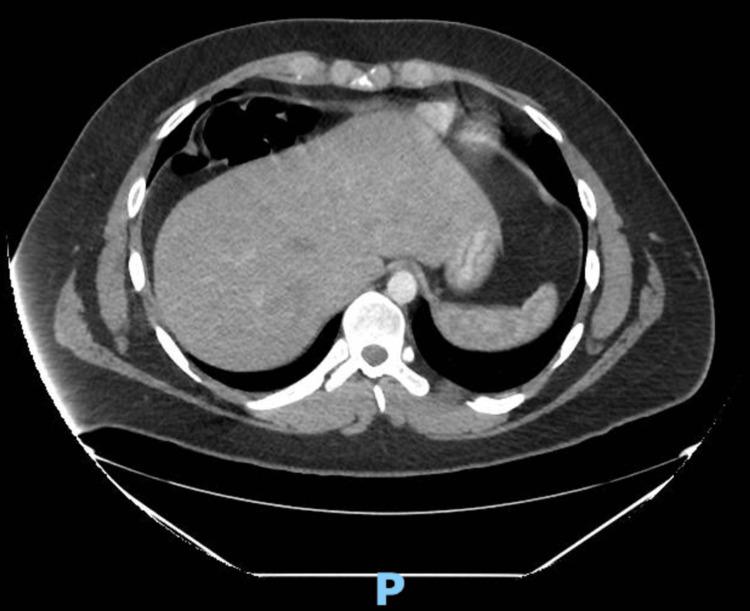

Chilaiditi's sign (colonic interposition) is a rare anomaly due to an abnormally located portion of the colon that is interposed in between the liver and the diaphragm. This rare anomaly is often incidentally seen on chest or abdominal radiographs. Chilaiditi's radiographic sign is usually asymptomatic, whereas the medical condition accompanied by clinical symptoms is termed Chilaiditi's syndrome. Possible causes of the syndrome include a long and mobile colon, scarring of the liver (cirrhosis), ascites, long-standing lung disease, as well as laxity of the falciform ligament. The most common clinical signs of Chilaiditi's syndrome include gastrointestinal symptoms; however, clinical presentation can vary. This report describes a case of a 21-year-old male patient who presented with a longstanding history of left upper quadrant epigastric abdominal pain with diarrhea (six to eight loose watery stools). The patient was diagnosed with Crohn's colitis and had tried a myriad of medical therapies with no adequate response. He chose to seek a second opinion and was subsequently discovered to have Chilaiditi's syndrome via computed tomography (CT) and confirmed by barium enema. The patient then elected to undergo a right laparoscopic colectomy to resolve the symptoms. By postoperative day five, all symptoms had resolved including abdominal pain and diarrhea. Therefore, it is important to consider Chilaiditi's syndrome as a differential diagnosis in persons presenting with left upper quadrant pain and symptoms of Crohn's colitis, especially those treated with adequate medical therapy without alleviation of symptoms.

奇莱迪蒂氏征(结肠间位)是一种罕见的异常情况,是由于结肠的异常位置部分夹在肝脏和膈肌之间。这种罕见的异常情况常在胸部或腹部X光片上偶然发现。奇莱迪蒂氏X光征通常无症状,而伴有临床症状的病症则称为奇莱迪蒂氏综合征。该综合征的可能病因包括结肠冗长且活动度大、肝脏瘢痕形成(肝硬化)、腹水、长期肺部疾病以及镰状韧带松弛。奇莱迪蒂氏综合征最常见临床体征包括胃肠道症状;然而,临床表现可能有所不同。本报告描述了一名21岁男性患者的病例,该患者有左上腹上腹部长期疼痛伴腹泻(每天六至八次稀水样便)的病史。该患者被诊断为克罗恩氏结肠炎,尝试了多种药物治疗但均无充分疗效。他选择寻求第二种意见,随后通过计算机断层扫描(CT)发现患有奇莱迪蒂氏综合征,并经钡剂灌肠证实。该患者随后选择接受右半结肠腹腔镜切除术以缓解症状。术后第五天,所有症状包括腹痛和腹泻均已缓解。因此,对于出现左上腹疼痛和克罗恩氏结肠炎症状的患者,尤其是那些接受了充分药物治疗但症状未缓解的患者,将奇莱迪蒂氏综合征作为鉴别诊断很重要。